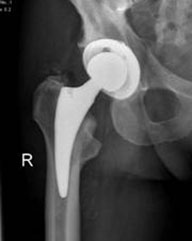

Es gibt verschiedene Modelle von künstlichen Hüftgelenken. Bei der Wahl der Prothese und ihrer Verankerung spielen unter anderem der Gesundheitszustand des Patienten, seine Knochenqualität und seine körperliche Aktivität eine Rolle. Ziel einer jeden Erstoperation ist es möglichst viel vom eigenen Knochen zu erhalten und die ursprüngliche Anatomie weitestgehend wiederherzustellen. Die Kunstgelenkmodelle, die dieser Aufgabe am besten gerecht werden, istdie Kurzschaftprothese. Diese können bei Patienten mit einem Lebensalter von unter circa 60 Jahren und guter Knochenqualität eingesetzt werden.

Das häufigste künstliche Hüftgelenk

Das künstliche Hüftgelenk, die sogenannte unzementierte Hüftendoprothese (Hüft-TEP), wird weltweit am häufigsten implantiert. Es besteht ein sehr langer Erfahrungszeitraum und man kann in den meisten Fällen eine hervorragende Funktion vorhersagen. Das Kunstgelenk wird in den Hüft- und Oberschenkelknochen passgenau eingebracht. Sowohl Gelenkspfanne als auch Hüftkopf werden dabei ersetzt. Sollte eine Knochenschwächung durch Osteoporose vorliegen, können die Gelenke mit Knochenzement sicher verankert werden (zementierte Hüftendoprothese).